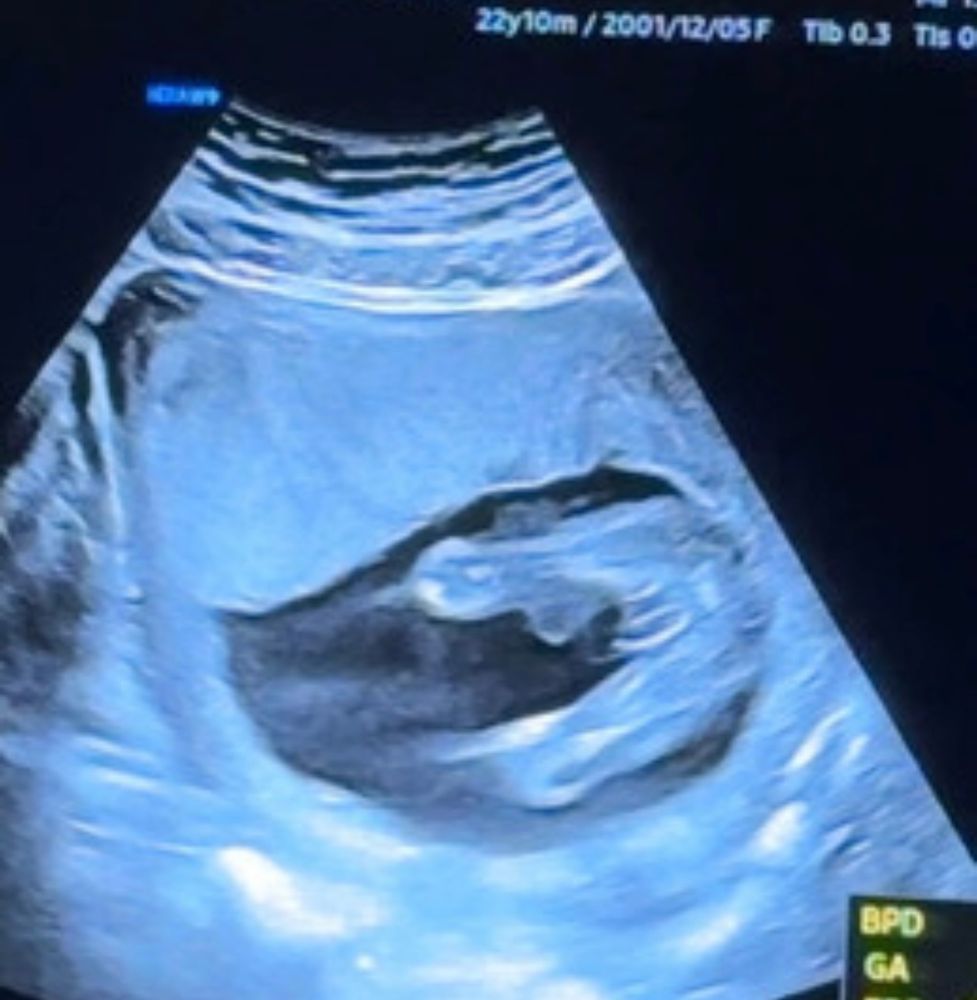

Девочки, как думаете кто у нас ? Врач предполагает Мальчик. 17 недель УЗИ 🥹❤️

Если это вид снизу то мне кажется девочка. Нам на 16 неделе уже четкий писюн показали😂 там спутать было невозможно

Евгения, Я не понимаю это УЗИ😂🙈

Врач сказал мальчик 🤷🏻♀️🙈

Севара, нет, нам с мужем тогда было не до фоток) сидели все в мониторах узи😁 но там прям чётко видно две ножки и половой орган, а у девочек говорят кофейное зёрнышко. Если на втором фото две ножки то там вроде как это зёрнышко есть)